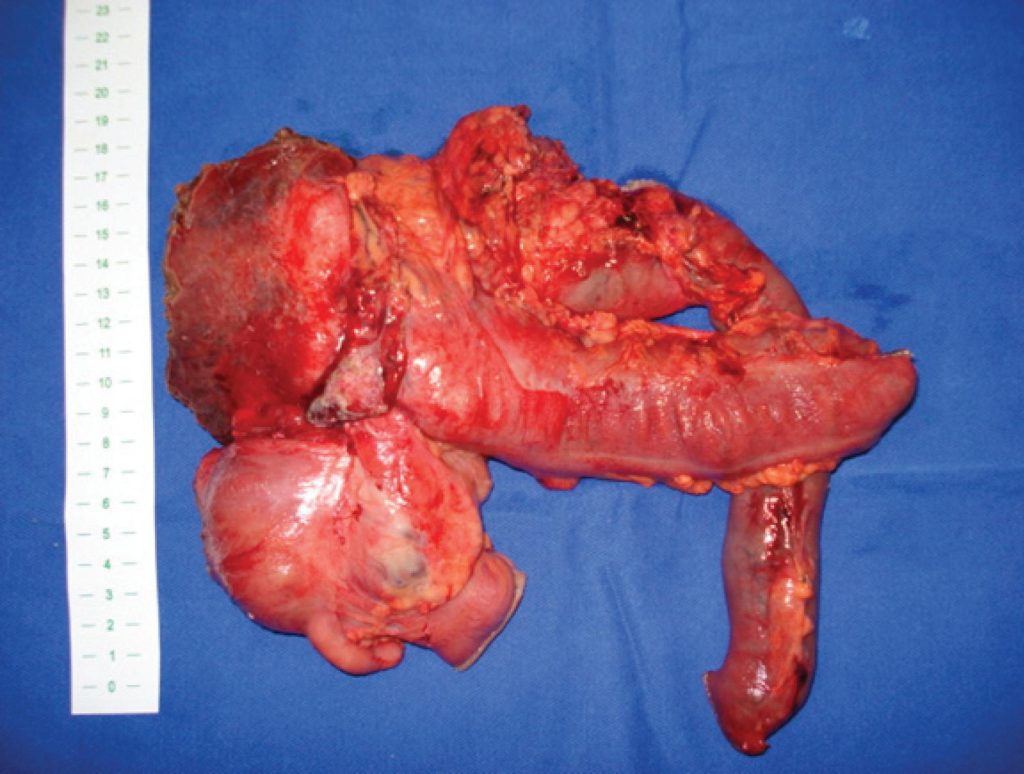

Pancreaticoduodenectomia e hemicolectomia direita em monobloco para o tratamento do câncer de cólon direito localmente avançado: relato de três casos

Embora os tumores colorretais sejam afecções cirúrgicas relativamente comuns, 5 a 12% dos casos são diagnosticados como localmente avançados (Tumores T4). Nessa situação particular, a eficácia da ressecção em monobloco já foi comprovada. Quando tumores do cólon direito invadem o duodeno proximal ou ainda a cabeça do pâncreas, um desafiador dilema é observado devido à complexidade do procedimento cirúrgico curativo. Dessa maneira, uma pancreaticoduodenectomia com hemicolectomia direita em monobloco deve ser realizada para se obterem margens livres. O presente artigo relata três casos de tumor de cólon direito localmente avançado com invasão do duodeno proximal. Todos esses casos foram submetidos à pancreaticoduodenectomia e hemicolectomia direita em monobloco de forma bem sucedida e sem mortalidade. Sobrevida em longo prazo foi observada em dois doentes (30 e 50 meses). No terceiro caso, o paciente não apresentava recidiva após 12 meses de seu tratamento cirúrgico. A ressecção multivisceral com pancreaticoduodenectomia em monobloco deve ser considerada em doentes com risco cirúrgico aceitável para cirurgia de grande porte e sem disseminação à distância. Essa conduta permanece justificada, pois a sobrevida a longo prazo dos doentes submetidos à ressecção radical (R0) é mais longa do que daqueles cuja ressecção é paliativa (R1-2).